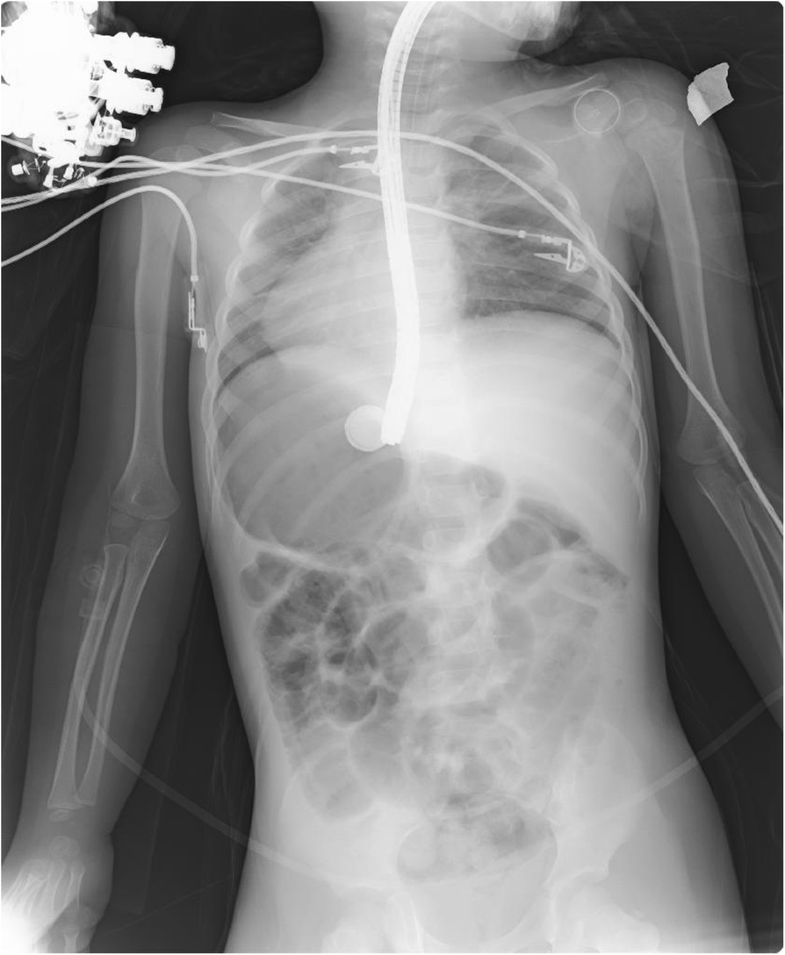

From www.researchgate.net

Abdominal radiograph of a child showing swallowed button batteries in How To Remove Button Battery From Stomach Most common intended use of both nonlithium and lithium of ingested button batteries in a national battery ingestion hotline review of 8648 cases 1 If a button battery is swallowed, it can cause damage to the wall of the bowel. A clear liquid diet (e.g. For batteries beyond the reach of the endoscope, surgical battery removal may be required in. How To Remove Button Battery From Stomach.